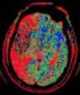

Decreased cerebral vascular transit time

Cerebral blood volume is the blood volume in a given amount of brain tissue. Pathophysiology The typical human adult's nerve skull contains approximately 1500 grams of the brain (including gray matter and white matter), 100-130 milliliters of blood, and 75 milliliters of cerebrospinal fluid. [Source: Wikipedia ]